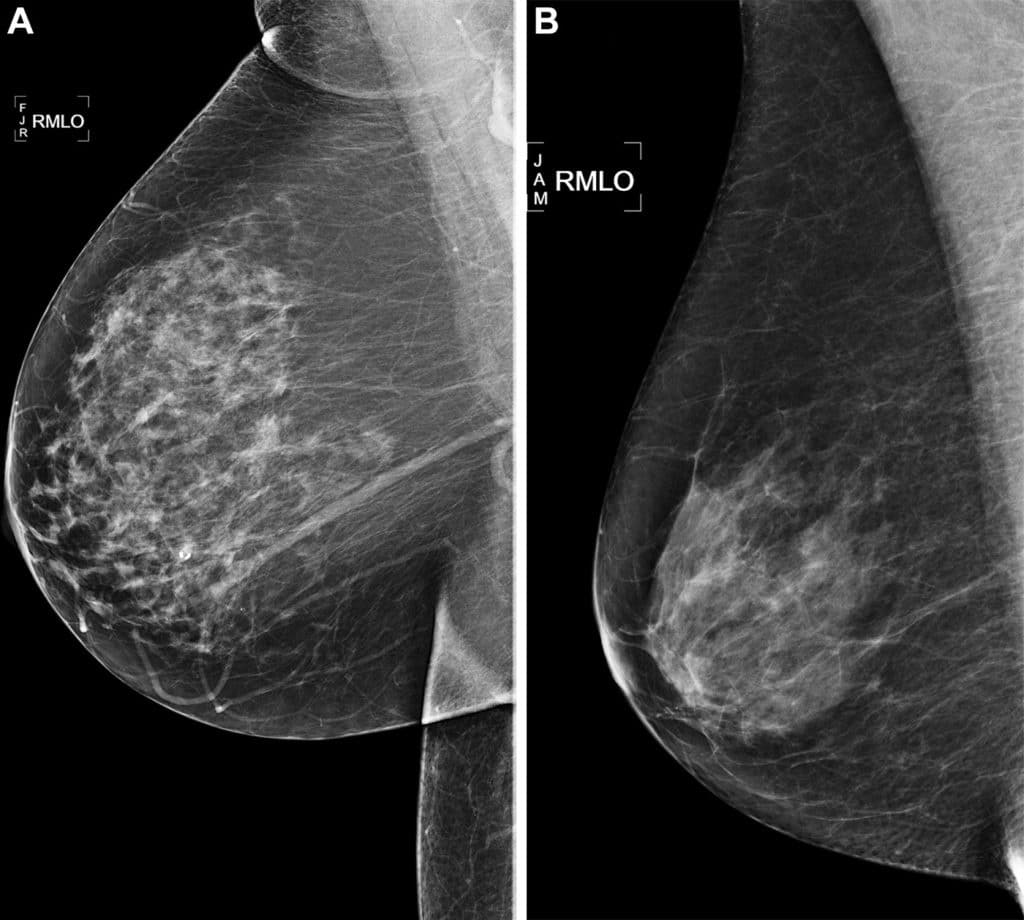

As mamografias de rastreamento oblíquas medial direito (RMLO) mostram resultados negativos de 2016 em (A) uma mulher de 73 anos com escore de risco de inteligência artificial (IA) Mirai com risco de mais de 90º percentil que desenvolveu câncer de mama direito em 2021 com 5 anos de acompanhamento e (B) uma mulher de 73 anos com escore de risco Mirai AI com risco inferior ao percentil 10 que não desenvolveu câncer em 5 anos após 5 anos de acompanhamento.